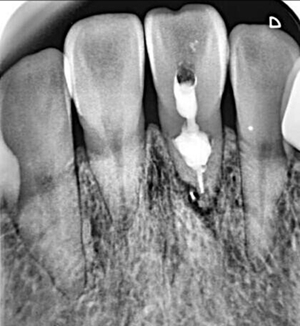

牙內(nèi)吸收通常無(wú)明顯癥狀。根據(jù)吸收的類型和原因,主要分為炎癥性吸收和替代性吸收。其中,炎癥性吸收可能繼發(fā)于前期牙本質(zhì)的細(xì)菌感染和創(chuàng)傷,牙本質(zhì)吸收過(guò)程的進(jìn)展不伴有吸收區(qū)鄰近部位硬組織的沉積,吸收部位可見(jiàn)大量肉芽組織,典型的影像學(xué)表現(xiàn)為,以根管為中心的橢圓形透光區(qū)。替代性吸收,導(dǎo)致根管內(nèi)牙本質(zhì)缺損的同時(shí),在缺損區(qū)某些部位還伴有骨樣組織的沉積,造成牙髓腔不規(guī)則的擴(kuò)大和根管連續(xù)性的破壞。根據(jù)牙內(nèi)吸收發(fā)生部位和嚴(yán)重程度的不同,又可呈現(xiàn)不同的征象。若吸收部位發(fā)展至牙冠,可以觀察到牙冠上出現(xiàn)粉紅色的點(diǎn),這是吸收細(xì)胞鄰近的結(jié)締組織高度血管化的結(jié)果。當(dāng)吸收部位位于根方,則可使得根管原有的形態(tài)缺失,X線片可見(jiàn)根管局部氣球樣的膨大,通常邊界清晰。若牙髓還有部分的活力,則患牙可能有慢性牙髓炎的表現(xiàn);若牙髓完全壞死,則可能發(fā)展成根尖周炎,而出現(xiàn)相應(yīng)的癥狀。竇道的出現(xiàn)往往是己發(fā)生慢性根尖膿腫或根管側(cè)穿的表現(xiàn)。由于患牙冠方的牙髓通常己經(jīng)壞死或被去除,因此敏感性測(cè)試常為陰性。

在一些病例中,牙內(nèi)吸收己經(jīng)發(fā)展至牙根外表面,使得根管與牙周相連通,并可能出現(xiàn)鄰近牙周組織的病變。這就需要在根管治療的同時(shí)行穿孔的修補(bǔ)。礦物三氧化物凝聚體(mineral trioxide aggregate,MTA)具有良好的生物相容性和誘導(dǎo)成骨性,對(duì)根尖周組織的刺激小,并且和其他材料相比,其封閉性也更好,故常用來(lái)做穿孔的修補(bǔ)。當(dāng)牙內(nèi)吸收的缺損不可修復(fù)時(shí),則只有選擇拔除。